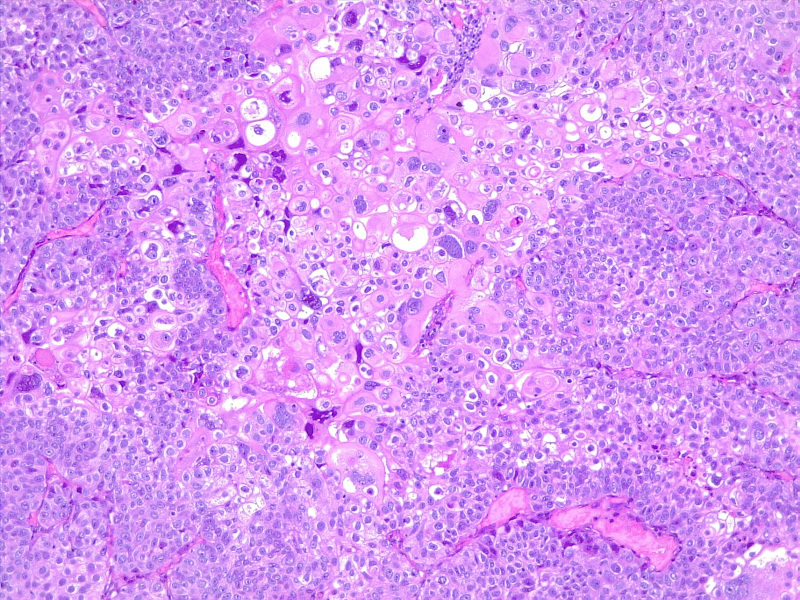

图2:膀胱炎和腺体的原位尿路上皮癌。由维基媒体 CoRus13 提供(公共领域 https://creativecommons.org/publicdomain/zero/1.0/deed.en)